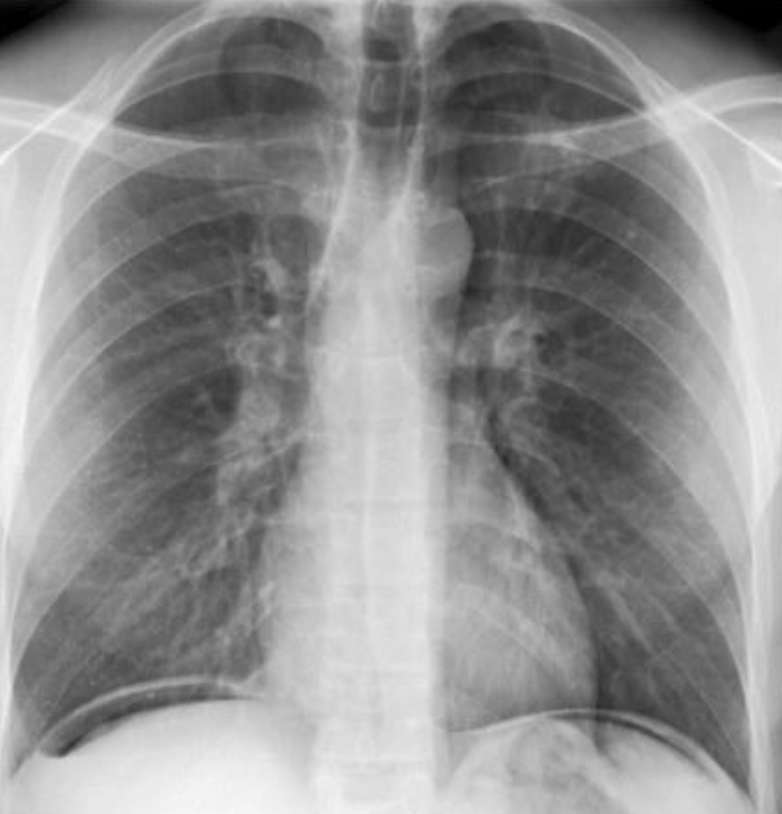

Female patient presents with chest pain and fever

- Modality ? Plain X-ray

- Findings ? Ipsilateral shifting of trachea and heart to the abnormal side - hemithorax

- Diagnosis? Pneumonia Collapse